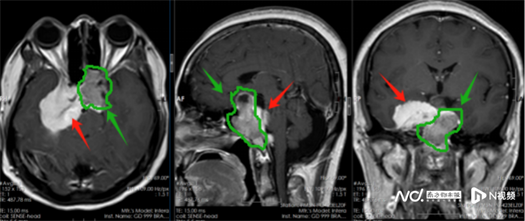

该院副院长鲁明接诊后,发现患者鞍区占位约3cm,压迫视神经引起视力下降,考虑为垂体瘤;蝶骨嵴、海绵窦、斜坡占位约5.2cm,引起颅高压症状,考虑为脑膜瘤。尽管两个肿瘤相邻,但体积均较大且位置特殊,难以一次性切除。

术前影像:绿色箭头考虑为垂体瘤,红色箭头考虑为脑膜瘤。